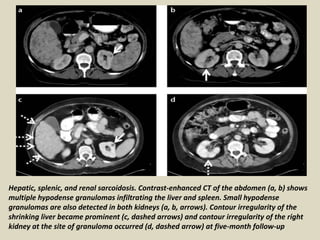

Hepatic, splenic, and renal sarcoidosis. Contrast-enhanced CT of the abdomen (a, b) shows

multiple hypodense granulomas infiltrating the liver and spleen. Small hypodense

granulomas are also detected in both kidneys (a, b, arrows). Contour irregularity of the

shrinking liver became prominent (c, dashed arrows) and contour irregularity of the right

kidney at the site of granuloma occurred (d, dashed arrow) at five-month follow-up